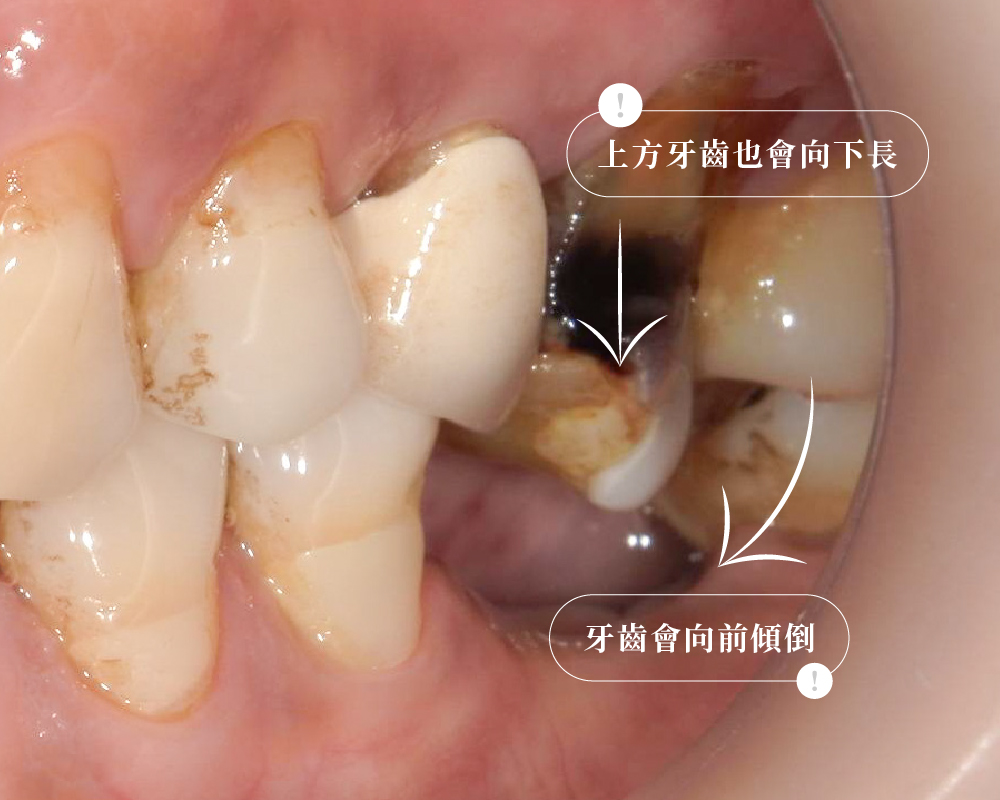

很多人以為缺牙就是先空在那裡,等以後想補再補。

但實際上,缺牙的位置不會一直乖乖留著。時間一久,旁邊的牙齒會慢慢倒過來、往中間擠;原本一顆大牙該有的空間,可能最後只剩下一點點。甚至連連樓上的鄰居也要湊熱鬧,上面的牙齒也會因為失去原本的對咬支撐而往下伸長,讓空間變得更擁擠。

所以有些人來評估時,看起來只是少一顆牙,實際上卻已經變成空間不足、咬合干擾、修復難度增加的問題。